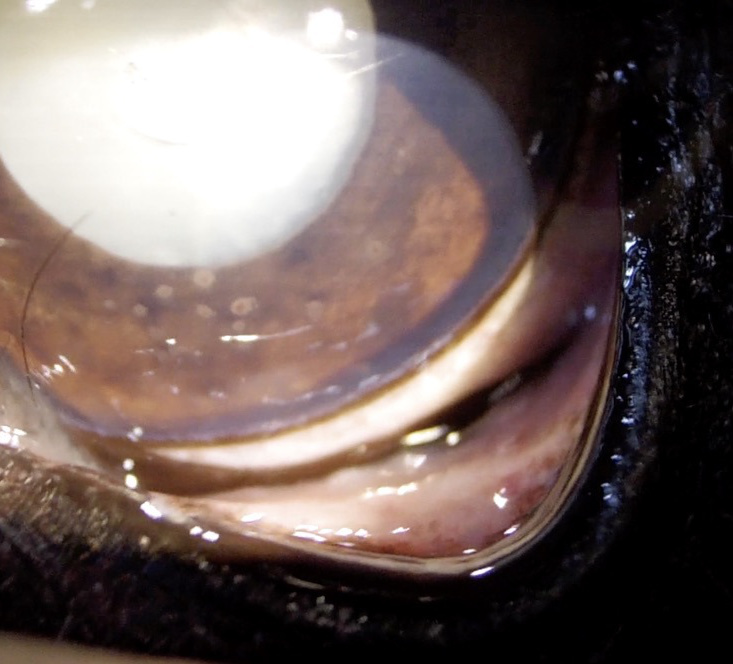

成熟白内障

水晶体の混濁が全体にわたり、視覚がない状態になります。

白内障(成熟)

白内障手術前